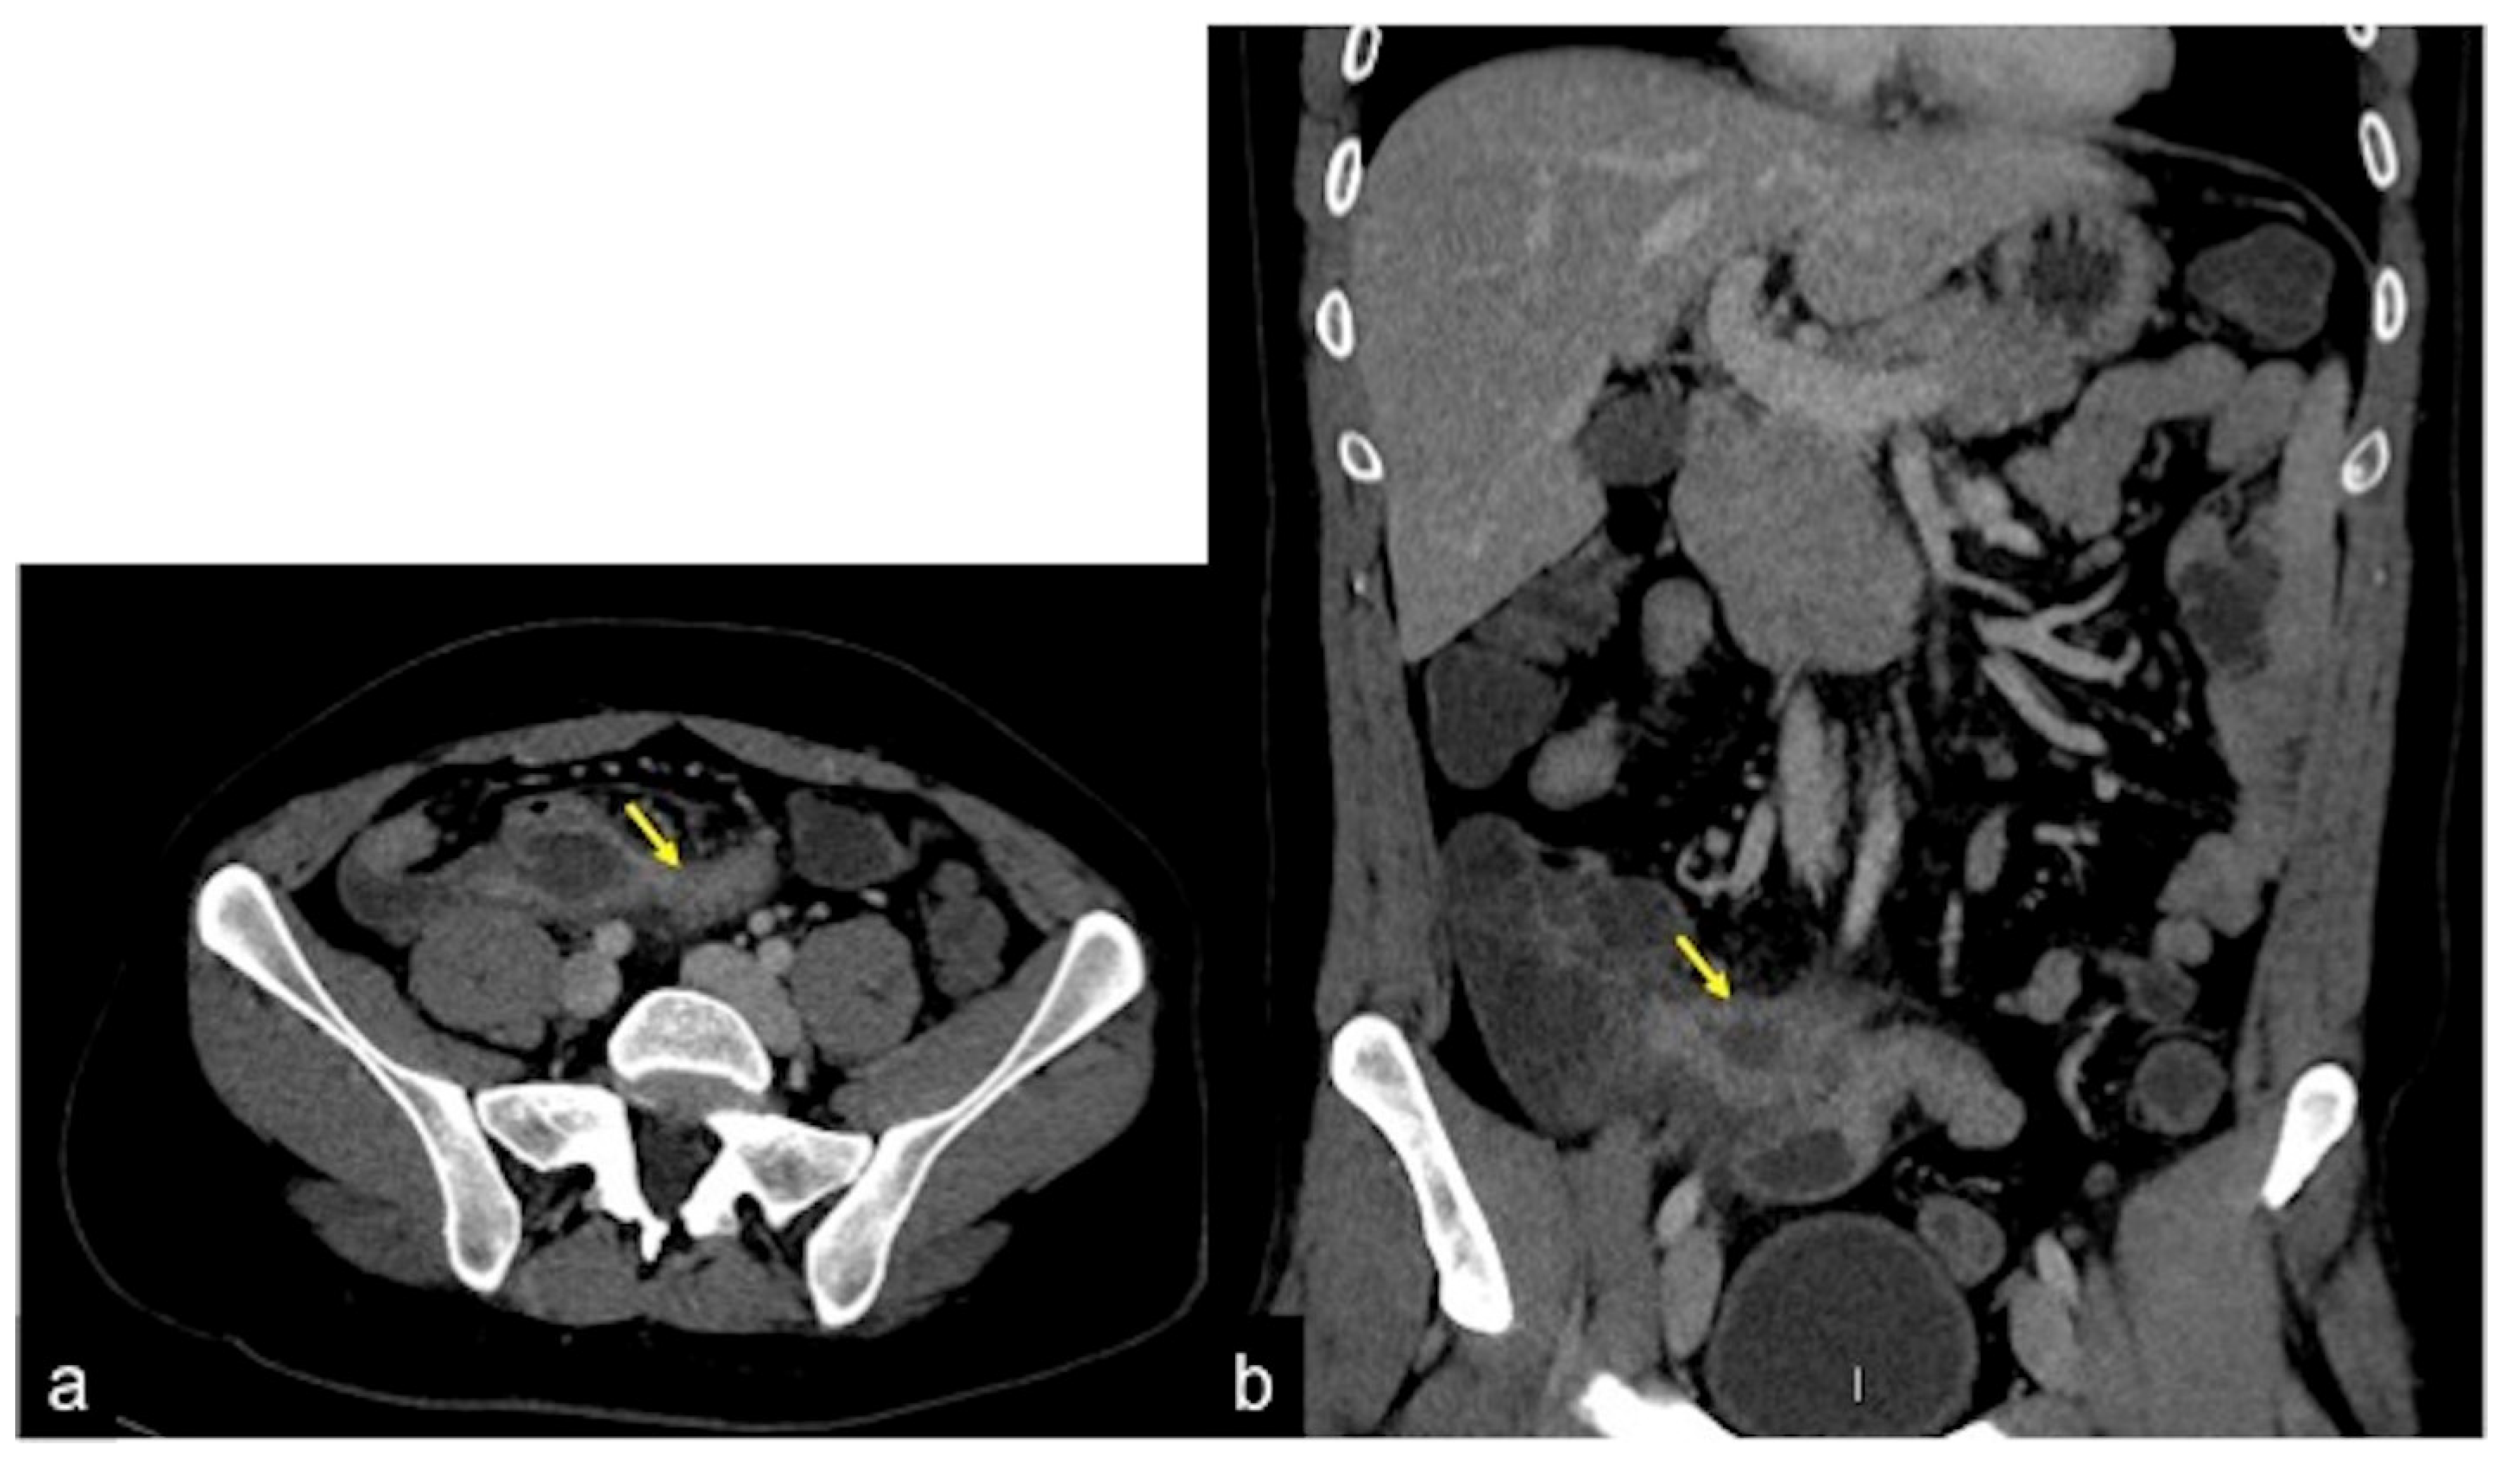

| Meckel’s Diverticulum (Figure 30) | Asymptomatic or, rarely, massive gastrointestinal bleeding. | A diverticulum with fluid or air content originating from the antimesenteric side of the distal ileum. |